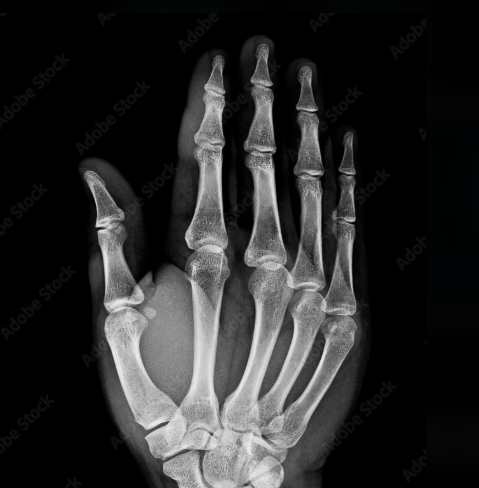

- 그런데 아내의 손을 대봤을 때...

💀 충격적인 순간

아내 베르타의 뼈가 그대로 보였어요.

손가락 뼈와 결혼반지까지! "여보... 이게 뭐죠?" 베르타는 무서워했지만,

뢴트겐은 깨달았습니다. 이 미지의 광선이 인체 내부를 볼 수 있다는 것을.